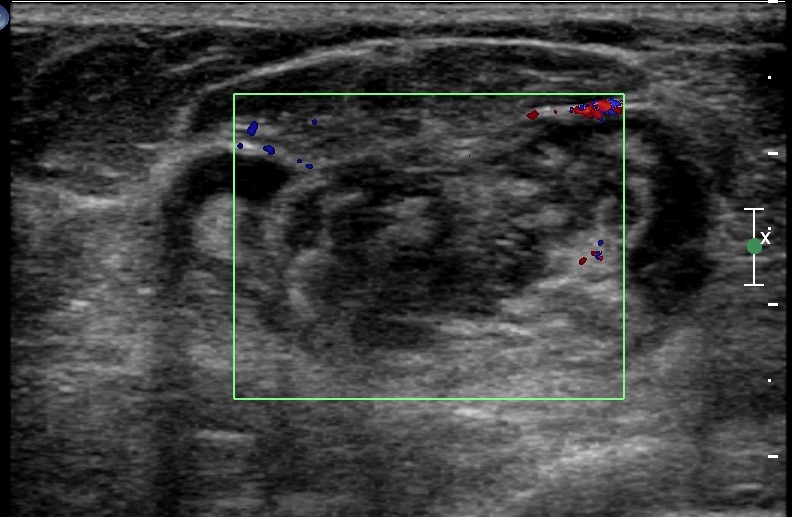

Physical examination revealed a 6.0?×?5.0 cm mass in the left breast. Mammography demonstrated an irregular, fat-containing, heterogeneous mass with circumscribed margins in the upper outer quadrant of left breast. Few scattered foci of coarse calcification were present within the mass. Breast sonography revealed an irregular, parallel, hyperechoic mass with circumscribed margins and no posterior acoustic features in the left breast at 3 o’clock position. Mild vascularity was observed on Color Doppler imaging. Contrast enhanced ultrasound (CEUS) done out of academic interest showed ill-defined, heterogenous enhancing mass, showing irregular shape, having surrounding vessels. Quantitative analysis showed higher PI (pulsatility index), AUC (area under curve) and lower TTP (time to peak) compared to normal tissue. The mass was assessed as Breast Imaging Reporting and Data System category 4b, and ultrasound-guided 14-gauge core biopsy revealed a biphasic tumor composed of bilayered ductal epithelium compressed by the proliferating stroma into leaf like architecture, The stromal cells showed increased cellularity, marked nuclear atypia and pleomorphism with round to oval nuclei, opened up chromatin, prominent nucleoli and moderate to abundant cytoplasm with many bizarre looking tumor giant cells. The stroma showed extensive heterologous lipomatous differentiation composed of neoplastic adipocytes as well as few lipoblasts. Mitosis was 3-4/10/hpf. Final histopathological diagnosis of malignant Phyllodes tumor with liposarcomatous differentiation was given. CT scan chest was done to look for lung metastasis, which revealed an irregular soft tissue mass in left breast with internal focal areas of fat attenuation. No nodules were seen in the lungs. Subsequent lumpectomy was performed and the gross specimen showed a well-demarcated tumor, measuring?6.8?×?6.5 × 3 cm. There were considerable bright yellow fatty components and some cleft-like spaces. Microscopically, the tumor exhibited a typical leaf-like growth pattern with extensive stromal overgrowth and stromal hypercellularity. Extensive areas of lipomatous differentiation were seen ranging from mature adipocytes to lipoblasts showing marked stromal atypia and irregularity. Mitotc activity was 7-8/10hpf. IHC for MDM2 was negative. Overall features were of malignant phyllodes tumor with well differentiated liposarcomatous differentiation.